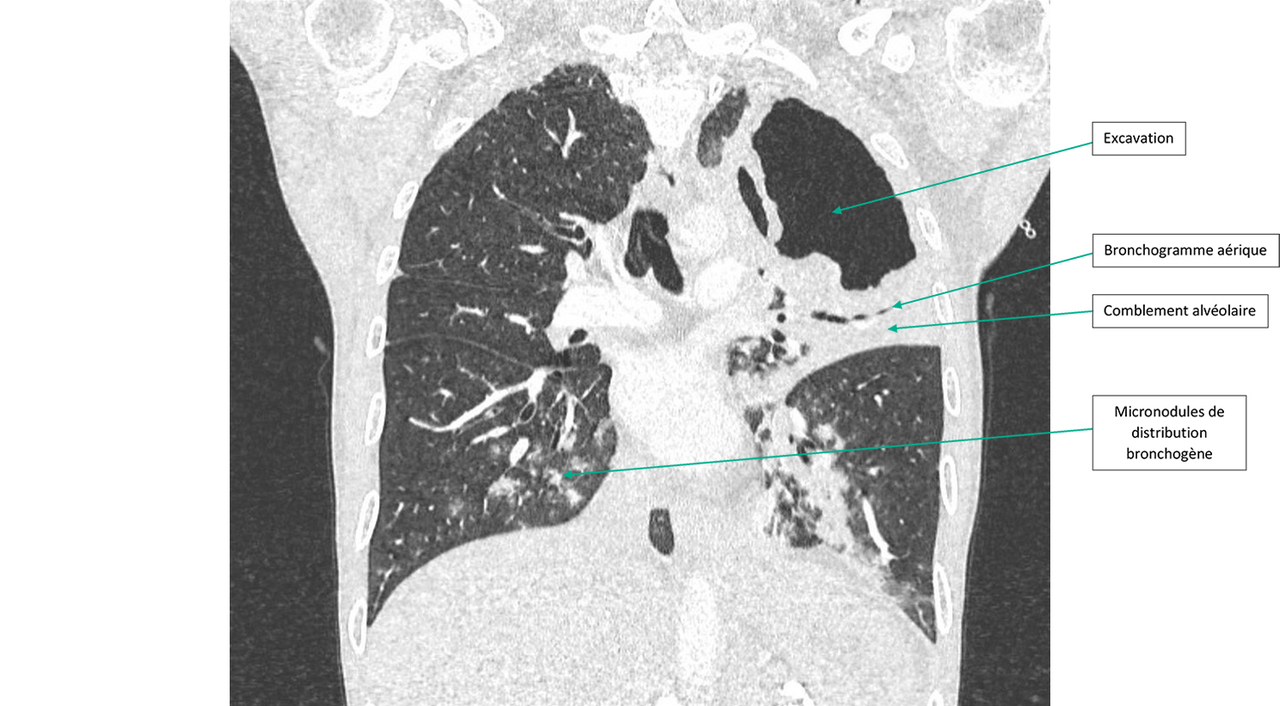

Figure 1 (Ariane Amoura, La Revue du Praticien)

Question 1 - Quelle(s) anomalie(s) observez-vous sur ce scanner ?

Il a une caverne du lobe supérieur gauche.

Il y a une opacité systématisée sur lobe supérieur gauche avec bronchogramme aérique en son sein.

On retrouve aux deux lobes inférieurs des micronodules de distribution bronchogène dits « en arbre en bourgeons ».

Il s’agit d’un scanner du thorax en coupe frontale et en fenêtre parenchymateuse. On ne retrouve pas d’embolie pulmonaire mais on observe une lésion excavée lobaire supérieure gauche de grande taille avec une condensation alvéolaire péri-lésionnelle avec bronchogramme aérique. Dans les lobes inférieurs, il y a des micronodules centrés sur des bronches (distribution bronchogène ou en arbre en bourgeons).